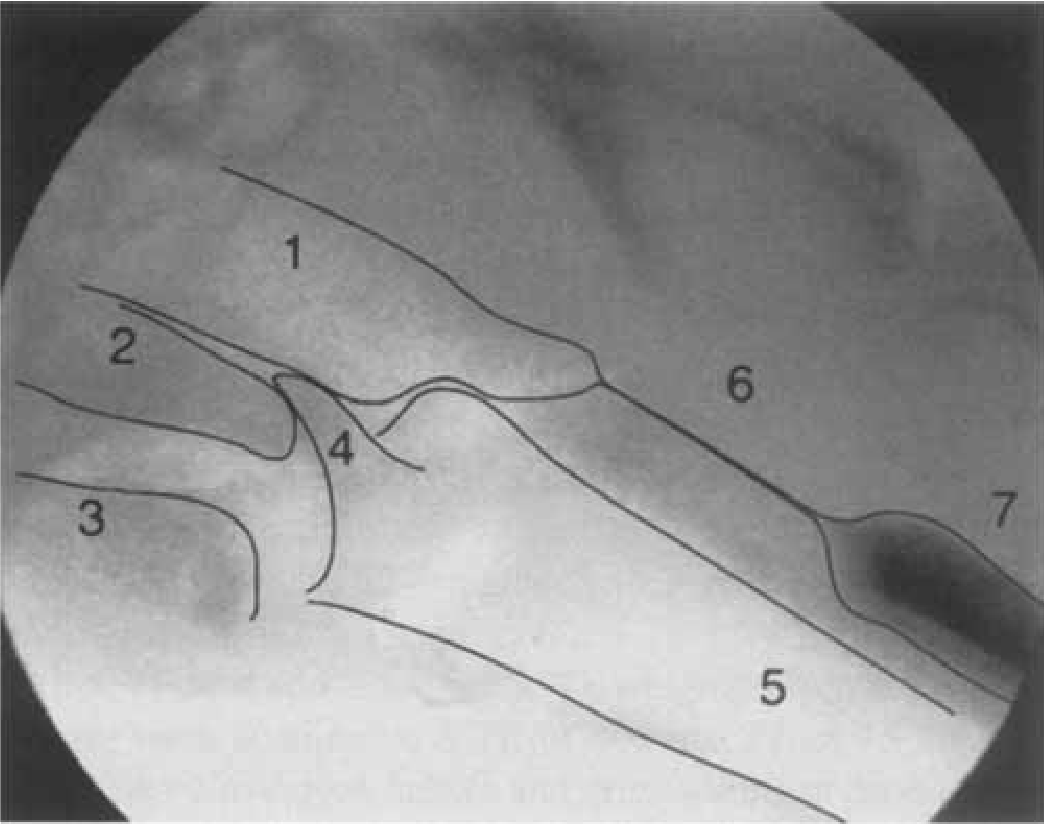

Name the numbered structures in this image